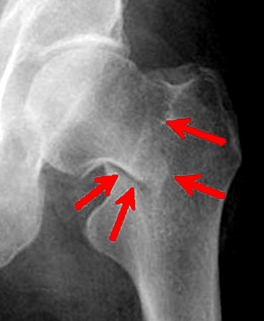

Перелом шейки бедра

Под переломом шейки бедра подразумевают три вида переломов: переломы в областях шейки, головки и большого вертела. По степени тяжести, боли они, безусловно, отличаются друг от друга. Но, тем не менее, принципы ухода более или менее одинаковы во всех этих случаях.  Если плоскость перелома проходит выше прикрепления капсулы тазобедренного сустава к бедру, переломы называются медиальными (срединными). Медиальные переломы шейки бедра - внутрисуставные. Линия медиального перелома может проходить вблизи перехода шейки в головку бедра, или через шейку.  Если плоскость перелома проходит ниже прикрепления капсулы сустава к шейке бедра, перелом называется латеральным (боковым), или вертельным. Bсе боковые переломы внесуставные.  С рентгенологической точки зрения переломы шейки детализируются в классификации Pauwels 1935 [10], в основе которой лежит деление переломов шейки по величине угла, образованного линией перелома с горизонталью, проведенной через вершины вертлужных впадин по рентгенограммам, произведенным в фасной проекции, выделено 3 типа:

Данная классификация определяет прогноз лечения. Так при горизонтальном I типе перелома сращение его наступает чаще, но статистически достоверно установлено, что чаще развивается асептический некроз головки бедренной кости (АНГБК). При вертикальном III типе перелом реже срастается и реже осложняется АНГБК. Поэтому при выборе способа лечения в первом случае следует остановиться на остеосинтезе, во втором случае отдать предпочтение эндопротезированию. P.S.Garden в 1964 г. [7] разработал классификацию с учетом степени нарушения кровоснабжения головки в зависимости от характера смещения, которое определял по деформации медиального трабекулярного пучка: